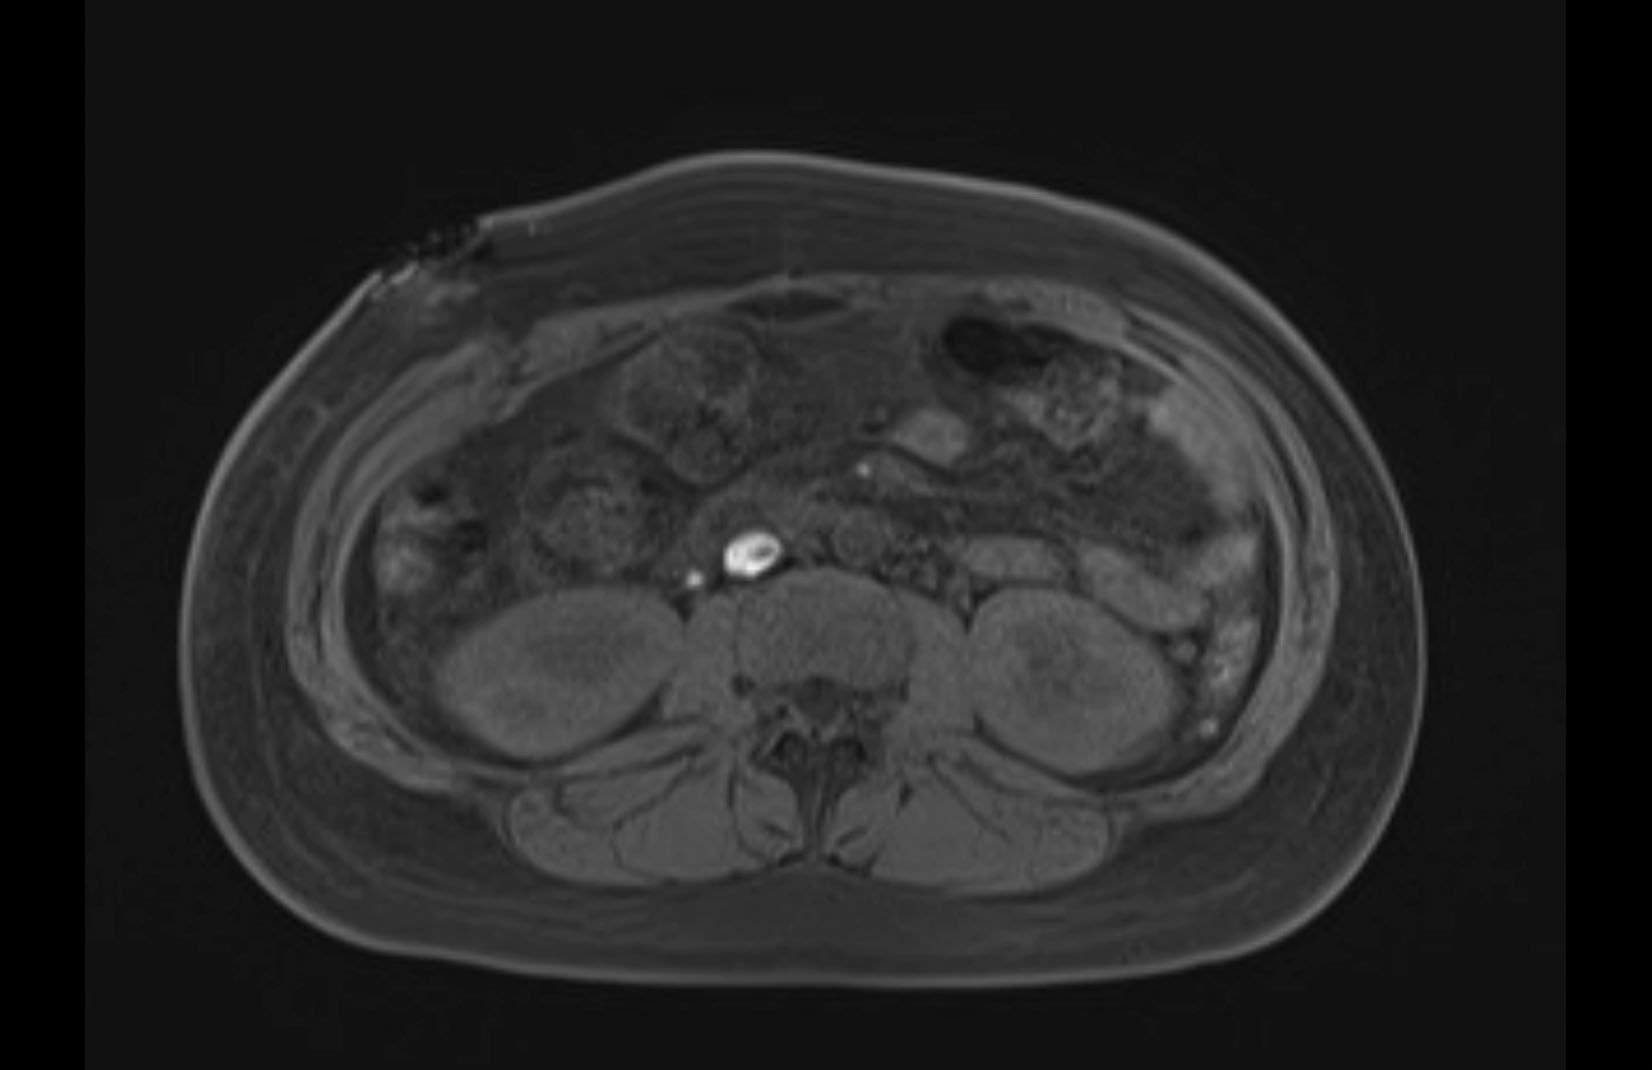

Imaging Analysis

Look through the patient's CT scan to identify any areas of concern for the necessary procedure.

MRI T1

MRI T2

Based on initial findings, which issue(s) would you be most concerned about?